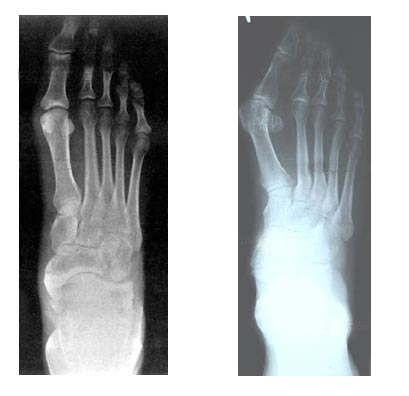

Kırık

Kemik dokusunun bütünlüğünün bozulmasıdır.

Kapalı Kırık; deri bütünlüğünün bozulmadığı, çevre dokuların çok fazla zarar görmediği kırıklardır.

Açık Kırık; kırık kemik uçlarının görülebildiği, çevre dokuların zarar gördüğü kırıklardır.

Kırıkta Belirti ve Bulgular:

• Ağrı,

• Morarma,  çürük, şişlik,

• Biçim bozukluğu (deformite), simetride bozulma,

• Hareket edememe, hareket kısıtlanması.